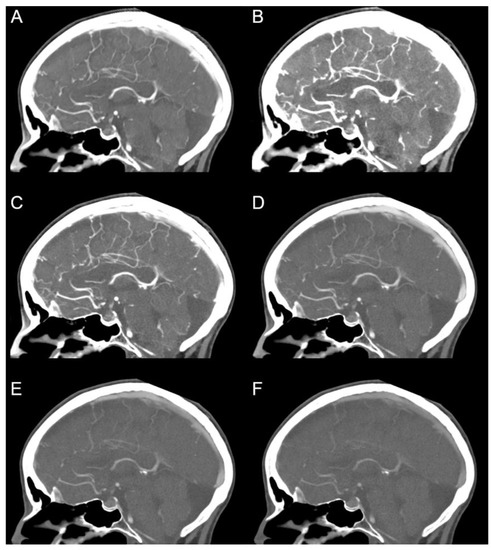

| Qualitative Analysis | PER | MER | p-Value |

|---|---|---|---|

| Intracranial large arteries | 4.82 ± 0.42 | 4.54 ± 0.53 (50 keV) | <0.001 |

| Small intracranial arteries | 4.91 ± 0.41 | 4.39 ± 0.66 (65 keV) | <0.001 |

| Contrast | 4.85 ± 0.36 | 4.76 ± 0.43 (40 keV) | 0.057 |

| Noise | 4.81 ± 0.43 | 4.28 ± 0.75 (60 keV) | <0.001 |